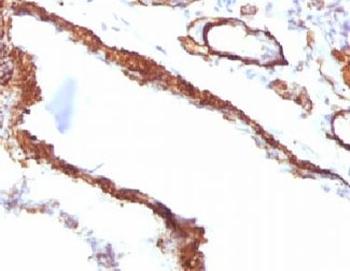

IHC: Formalin-fixed, paraffin-embedded Leiomyosarcoma stained with Smooth Muscle Actin antibody (clone SPM332).